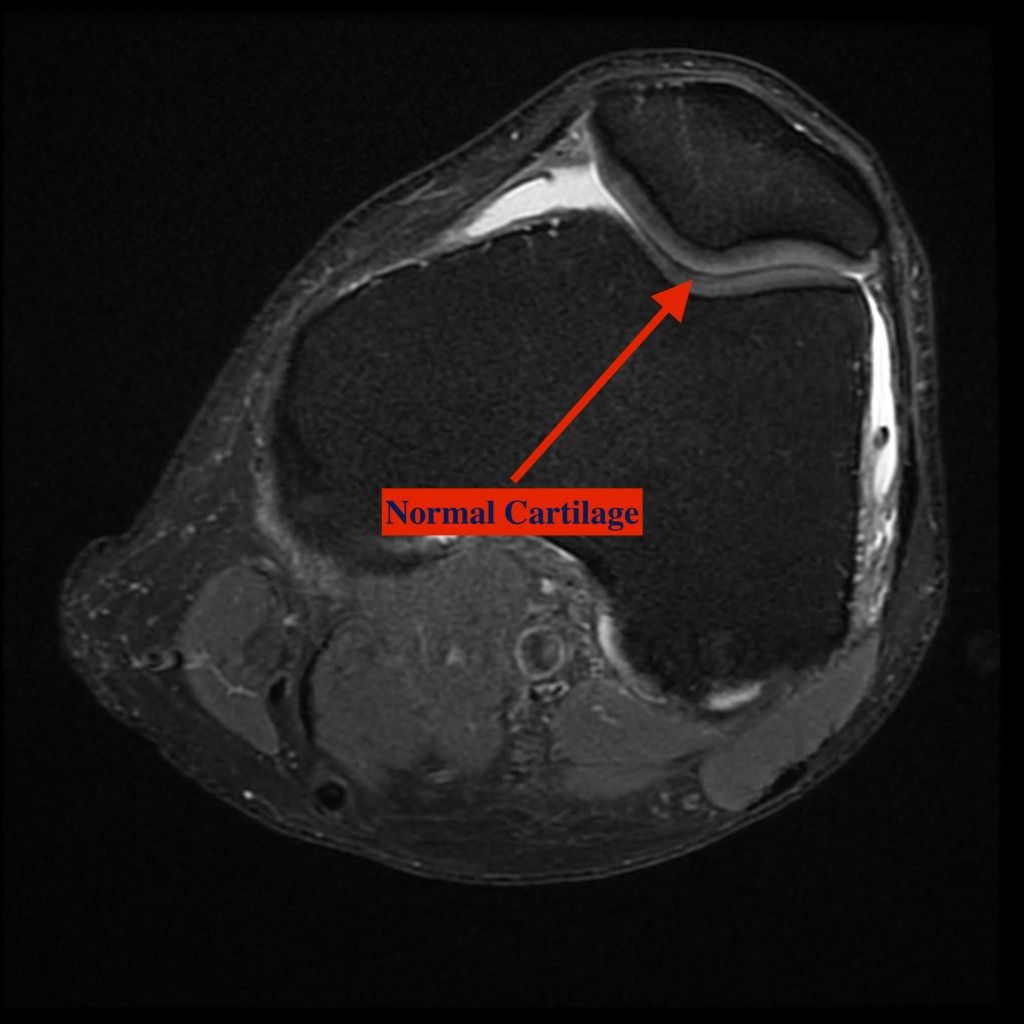

Patellofemoral arthritis occurs when the articular cartilage along the trochlear groove and on the underside of the patella wears down and becomes inflamed. When cartilage wears away, it becomes frayed and, when the wear is severe, the underlying bone may become exposed. Moving the bones along this rough surface may be painful.